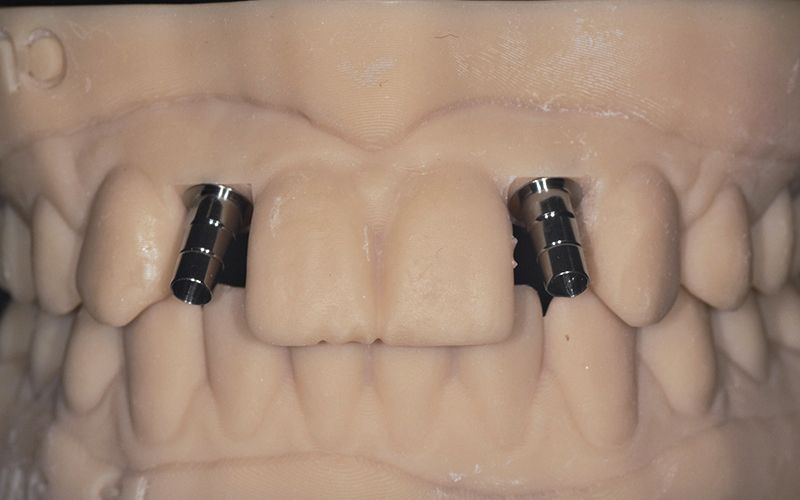

Las coronas de zirconio monolítico fresado con cut-back iban cementadas sobre dos bases de titanio previamente talladas para salvar el eje de inserción de los implantes.

Al cabo de unos días se hicieron los controles clínicos y radiológicos pertinentes y se procedió a cementar las dos coronas de forma definitiva dando por finalizada la rehabilitación por agenesia de los dos incisivos laterales 12 y 22.